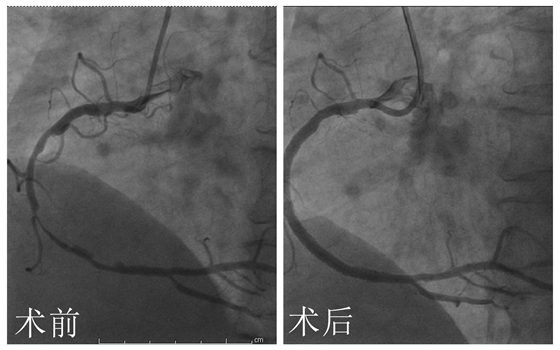

3月22日,彭道地主任及范爱德副主任医师同台完善冠脉造影+支架植入术示:冠脉血管多支多处严重狭窄,右冠弥漫性狭窄次全性闭塞,并在右冠病变处植入支架3枚,狭窄病变血管开通,症状也就随之消失了。